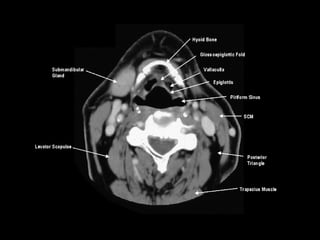

Radiographers use medical imaging equipment like X-rays and MRIs to produce images of patients' internal structures and organs. They are responsible for positioning patients, operating scanning machines, and ensuring quality images. Radiographers must have strong attention to detail, excellent communication skills, and the ability to work well under pressure to accurately capture anatomical features and diagnose any abnormalities.